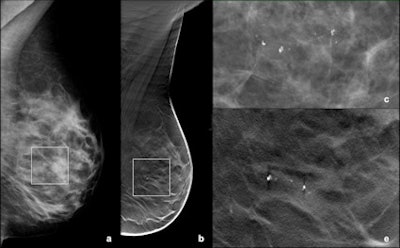

![A small cluster of heterogeneous microcalcifications was visible on FFDM (a: mediolateral oblique [MLO] view; c: particular digitally magnified) in the central, prepectoral, area of the right breast. The finding was clearly visible on DBT (b: MLO view; e, f: particular digitally magnified), and in both imaging modalities was classified as suspicious. The patient underwent vacuum-assisted biopsy and histology was intermediate grade DCIS. All images courtesy of Dr. Paola Clauser.](https://img.auntminnieeurope.com/files/base/smg/all/image/2015/04/ame.2015_04_30_09_21_35_578_2015_04_30_dbt_calcifications_pic1.png?auto=format%2Ccompress&fit=max&q=70&w=400)